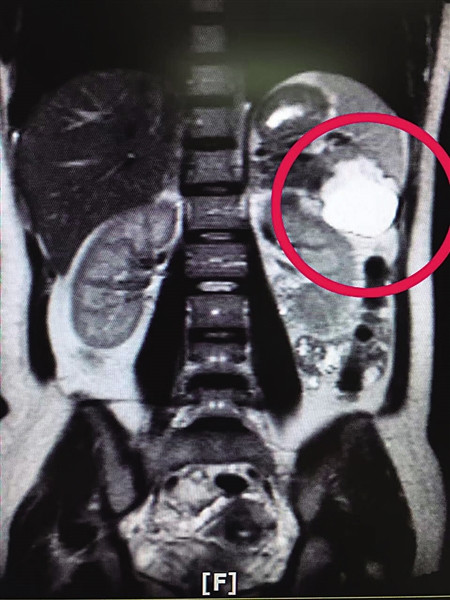

Ngày 12/7, Vương Đình lại đến bệnh viện để siêu âm, các bác sĩ vẫn không tìm thấy bào thai trong bụng cô. Họ nghi ngờ thai nhi có thể đang nằm ở đâu đó trong cơ thể của Vương Đình nên họ đã kiểm tra thêm các bộ phận khác như xương chậu, thân, gan, mật và tuyến tuỵ. Tuy nhiên, chỉ đến khi các bác sĩ siêu âm phần lá lách thì sự thật mới được phơi bày. Mọi người đều bất ngờ khi thấy một bào thai đang phát triển trong lá lách.

| Kết quả siêu âm cho thấy một bào thai đang phát triển trong lá lách của Vương Đình. |

Phó giám đốc bệnh viện Tây Nam cho rằng, đây là một trường hợp vô cùng hy hữu trên thế giới. Bởi trong các khả năng mang thai ngoài tử cung thì trứng thường sẽ rơi xuống xương chậu. Tuy nhiên, có thể là do quá trình thụ thai, buồng trứng của Vương Đình sau khi thụ tinh đã vô tình rơi ra, nhưng với sự vận động của ruột, buồng trứng này bất ngờ bị đẩy lên lá lách và vẫn phát triển cho đến khi bị phát hiện.